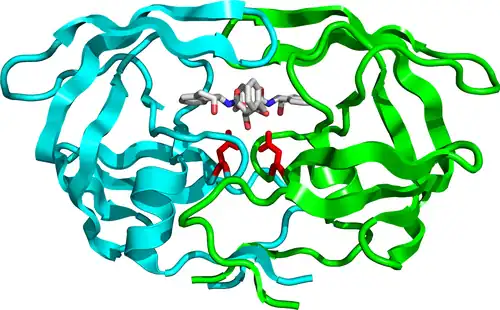

HIV-1 protease dimer in white and grey, with peptide substrate in black and active site aspartate side chains in red. (PDB: 1KJF) | |||||||||

Mature HIV protease exists as a 22 kDa homodimer, with each subunit made up of 99 amino acids.[1] A single active site lies between the identical subunits and has the characteristic Asp-Thr-Gly (Asp25, Thr26 and Gly27) catalytic triad sequence common to aspartic proteases.[8] As HIV-1 PR can only function as a dimer, the mature protease contains two Asp25 amino acids, one from each monomer, that act in conjunction with each other as the catalytic residues.[9] Additionally, HIV protease has two molecular "flaps" which move a distance of up to 7 Å when the enzyme becomes associated with a substrate.[10] This can be visualized with animations of the flaps opening and closing.